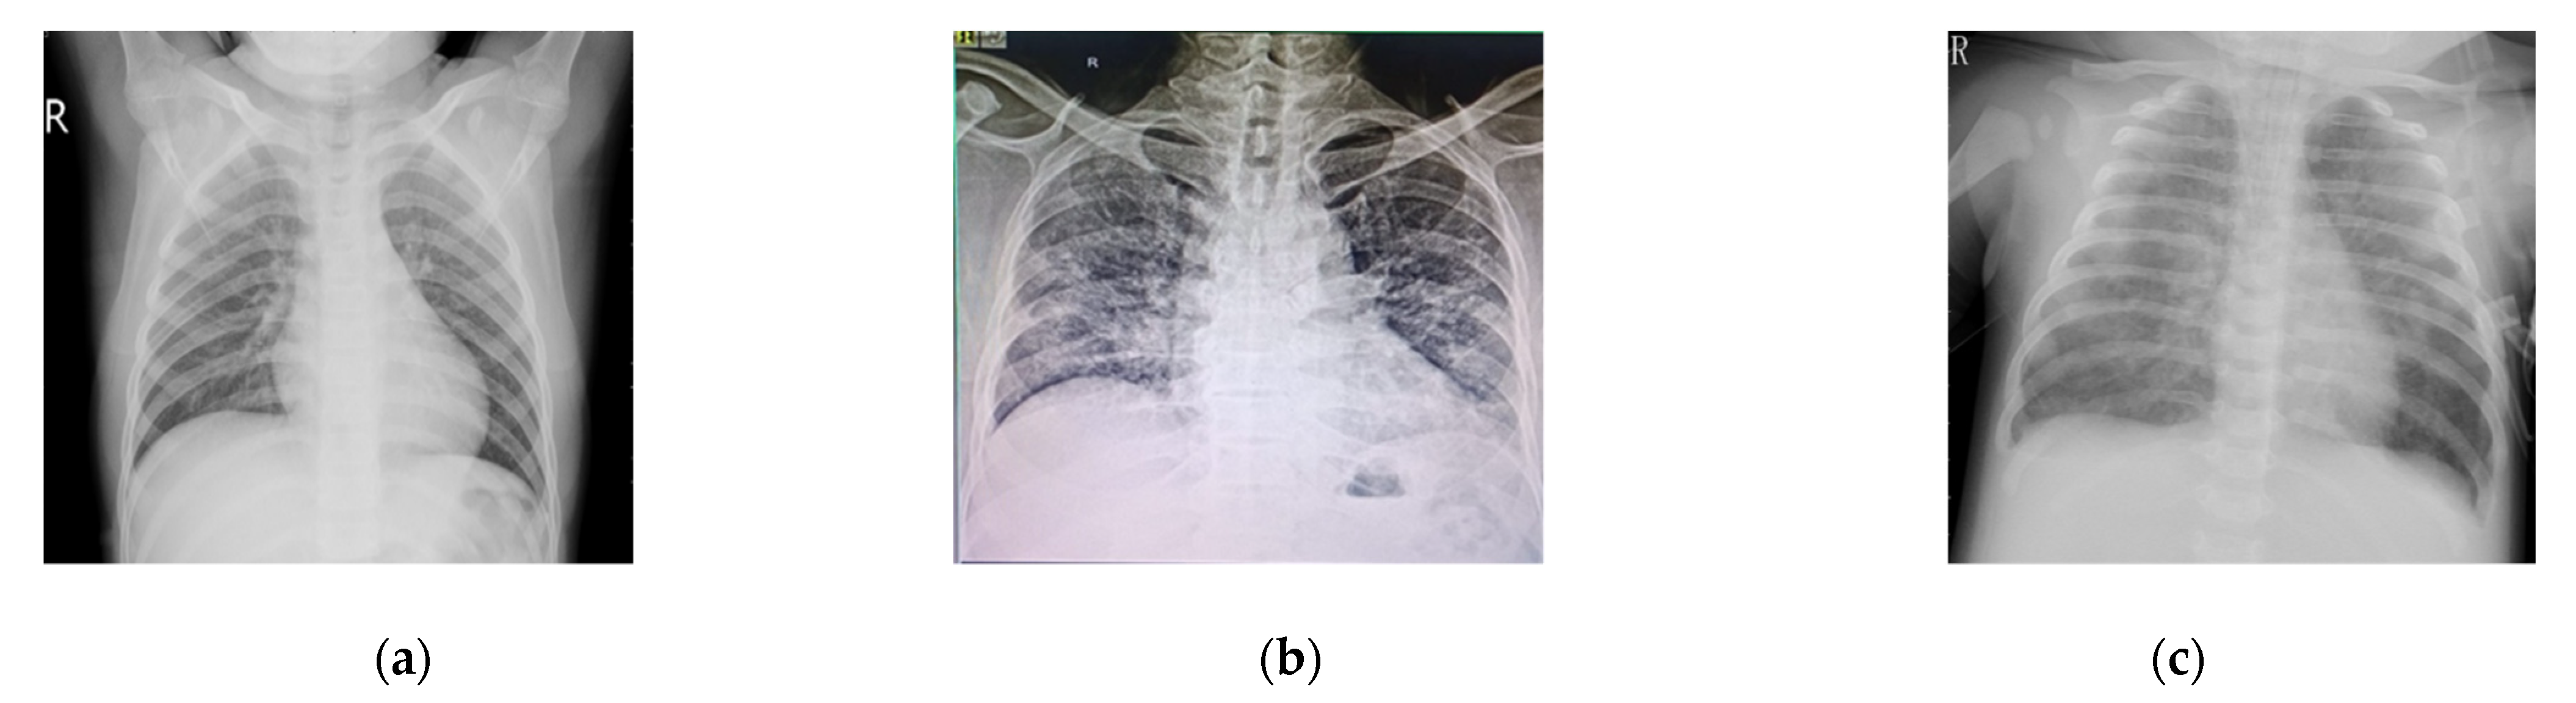

- GP stage where an Outpatient Department (OPD) based on symptoms refers for further PCR and X-ray chest to rule out the COVID-19.

- PCR test is negative on day 1 (the day of report) while the symptoms are clearly providing a COVID-19 picture and the X-ray is also suggesting COVID-19.

- PCR test has a negative result on day 3 again, while COVID-19 is suggested from the chest X-ray.